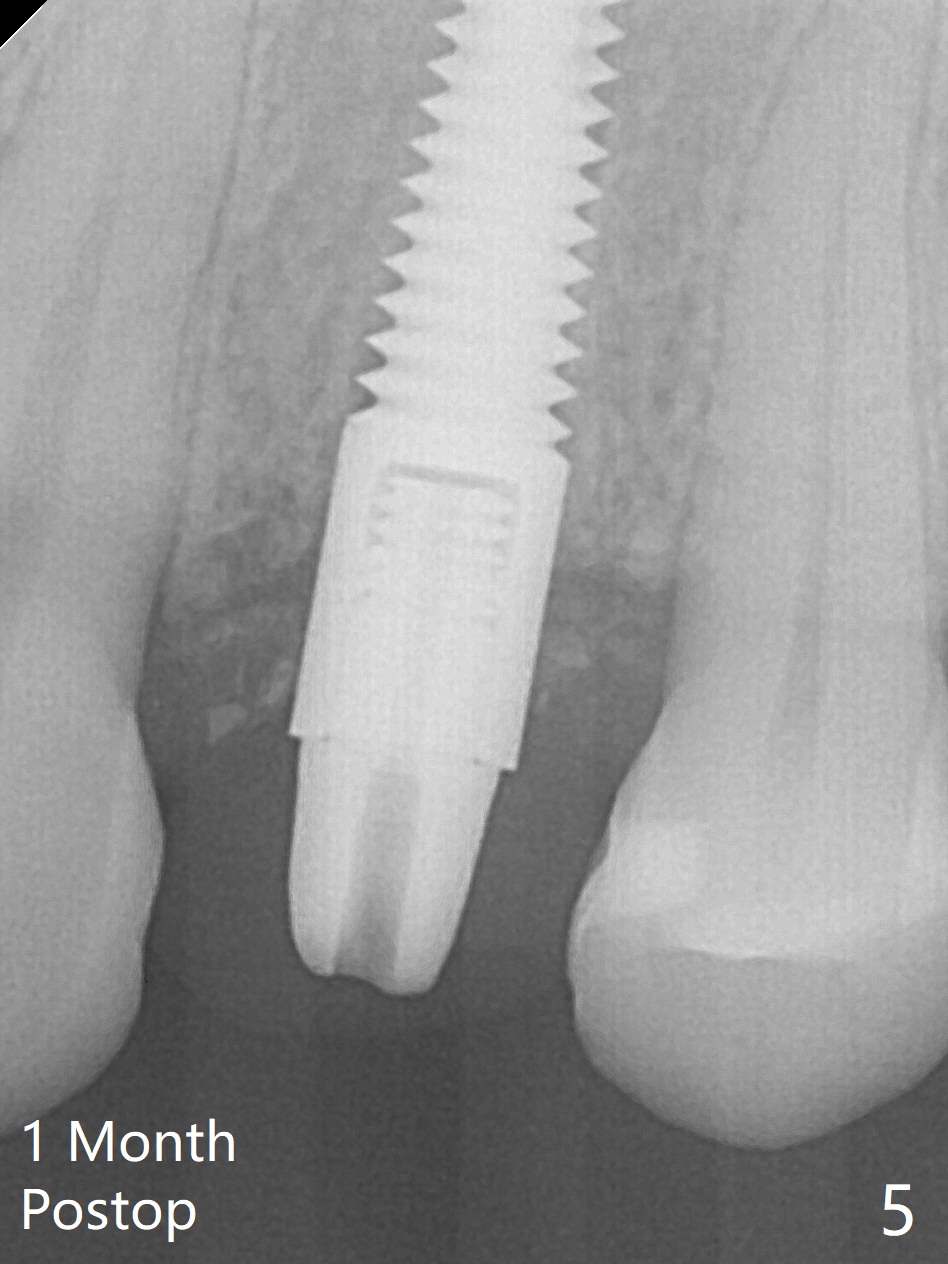

Since there is no buccal plate atrophy at 4, or 8, socket shield is not attempted at #31. Extraction turns out to be difficult because of tooth fracture. The buccal and palatal flaps have to be elevated minimally for tooth sectioning and purchase point formation. More surprising, a 4.5 mm implant appears to be too wide for the space; a 4x17 mm implant achieves insertion torque >60 Ncm (Fig.1,2). In fact Vanilla graft is placed before and after implantation. The advantage of bone graft before implant is that the graft is able to be placed as apical as possible to repair the apical defect if it is present. The disadvantage is hemorrhage. After placement of a 3.5x5 mm abutment, an immediate provisional is fabricated (Fig.3 P), which seems to be able to hold the separated buccal papillae in place. The latter heal around the immediate provisional 9 days postop (Fig.4). Because of the seal, the bone graft remains in place 1 month postop (Fig.5). There is no bone loss 5.5 months postop (Fig.6,7) or 6.5 months postop (immediately post cementation, Fig.8).